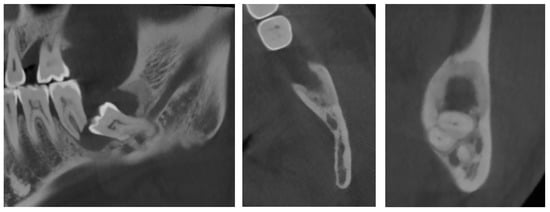

The complementary CBCT examination found that tooth #38 was directed mesially and slightly lingually (Figure 9) and that it had three roots, with the deformed IAC tortuously passaging between them. The crown of tooth #38 was close to the distal root of tooth #37, whose apex was strongly resorbed. The pericoronal osteolytic lesion measuring 24 × 10 × 10 mm extended from the crown-root junction of tooth #38 to the partially resorbed distal root of tooth #37. There was bone dehiscence of 12 mm on the alveolar crest and of 5 mm on the vestibular cortex. The borders of the lesion were in places irregular and strongly sclerotic, indicating a superimposed infection. There were no signs of bone sequestration, periosteal reaction or associated fracture. These findings supported the initial diagnosis of DC.

Figure 9.

CBCT X-ray of the case #3 patient.